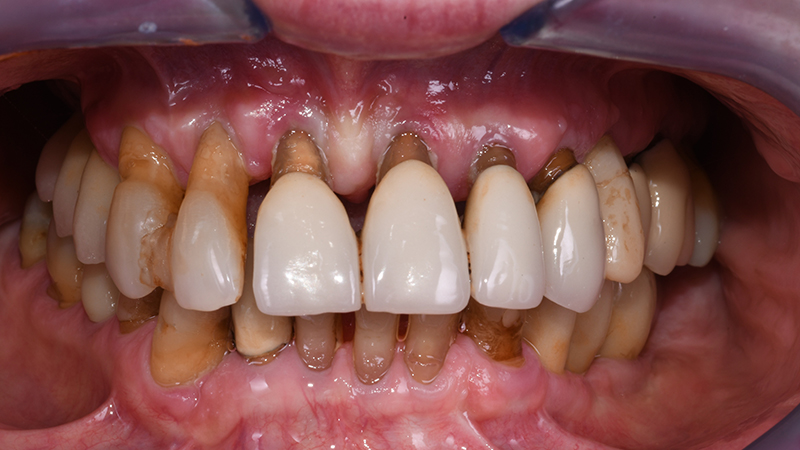

La paziente, donna di 70 anni e fumatrice di <5 e-cigarettes al giorno, afferisce inviata da Odontoiatra curante per valutazione estetico-funzionale del sestante 2 (mascellare anteriore). Riferisce di essere stata curata negli anni precedenti mediante terapie non chirurgiche e chirurgiche a seguito di diagnosi di parodontite e di seguire un regime personalizzato di terapia parodontale di supporto. Ciononostante lamenta insoddisfazione estetica dovuta alla presenza di ampi triangoli neri tra gli elementi dentari residui, migrazione degli stessi in direzione vestibolare nel corso degli anni, presenza di splint interdentali in composito, difformità cromatiche e morfologiche associate a discomfort alla fonazione e mobilità.

Ponendo vincoli relativamente alle tempistiche e richiedendo una riabilitazione protesica fissa, il piano di trattamento individuale è stato orientato verso riabilitazione protesica fissa a supporto impiantare a carico immediato per la sostituzione degli elementi 13-12-11-21-22-23-24 (Figs. 1, 2)

Sorriso in visione frontale intra-orale

Fig. 2 - Visione frontale intra-orale